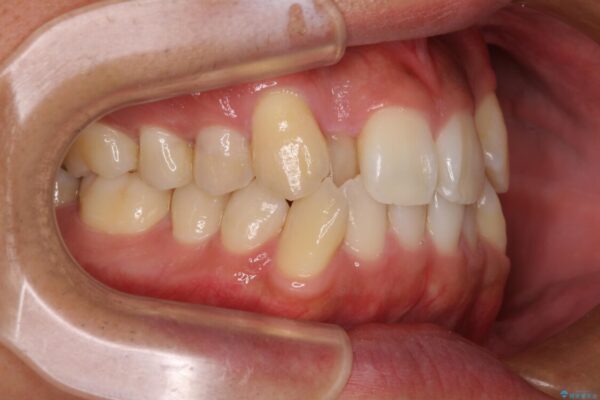

「八重歯を治したい」とご相談いただいた患者様の症例をご紹介します。

上下の前歯部に強い叢生(ガタガタの歯並び)があり、そのまま歯を並べると出っ歯になってしまう可能性がありました。

治療前

• 八重歯と前歯のガタガタを抜歯矯正で治療|クリアブラケット使用例 治療前画像